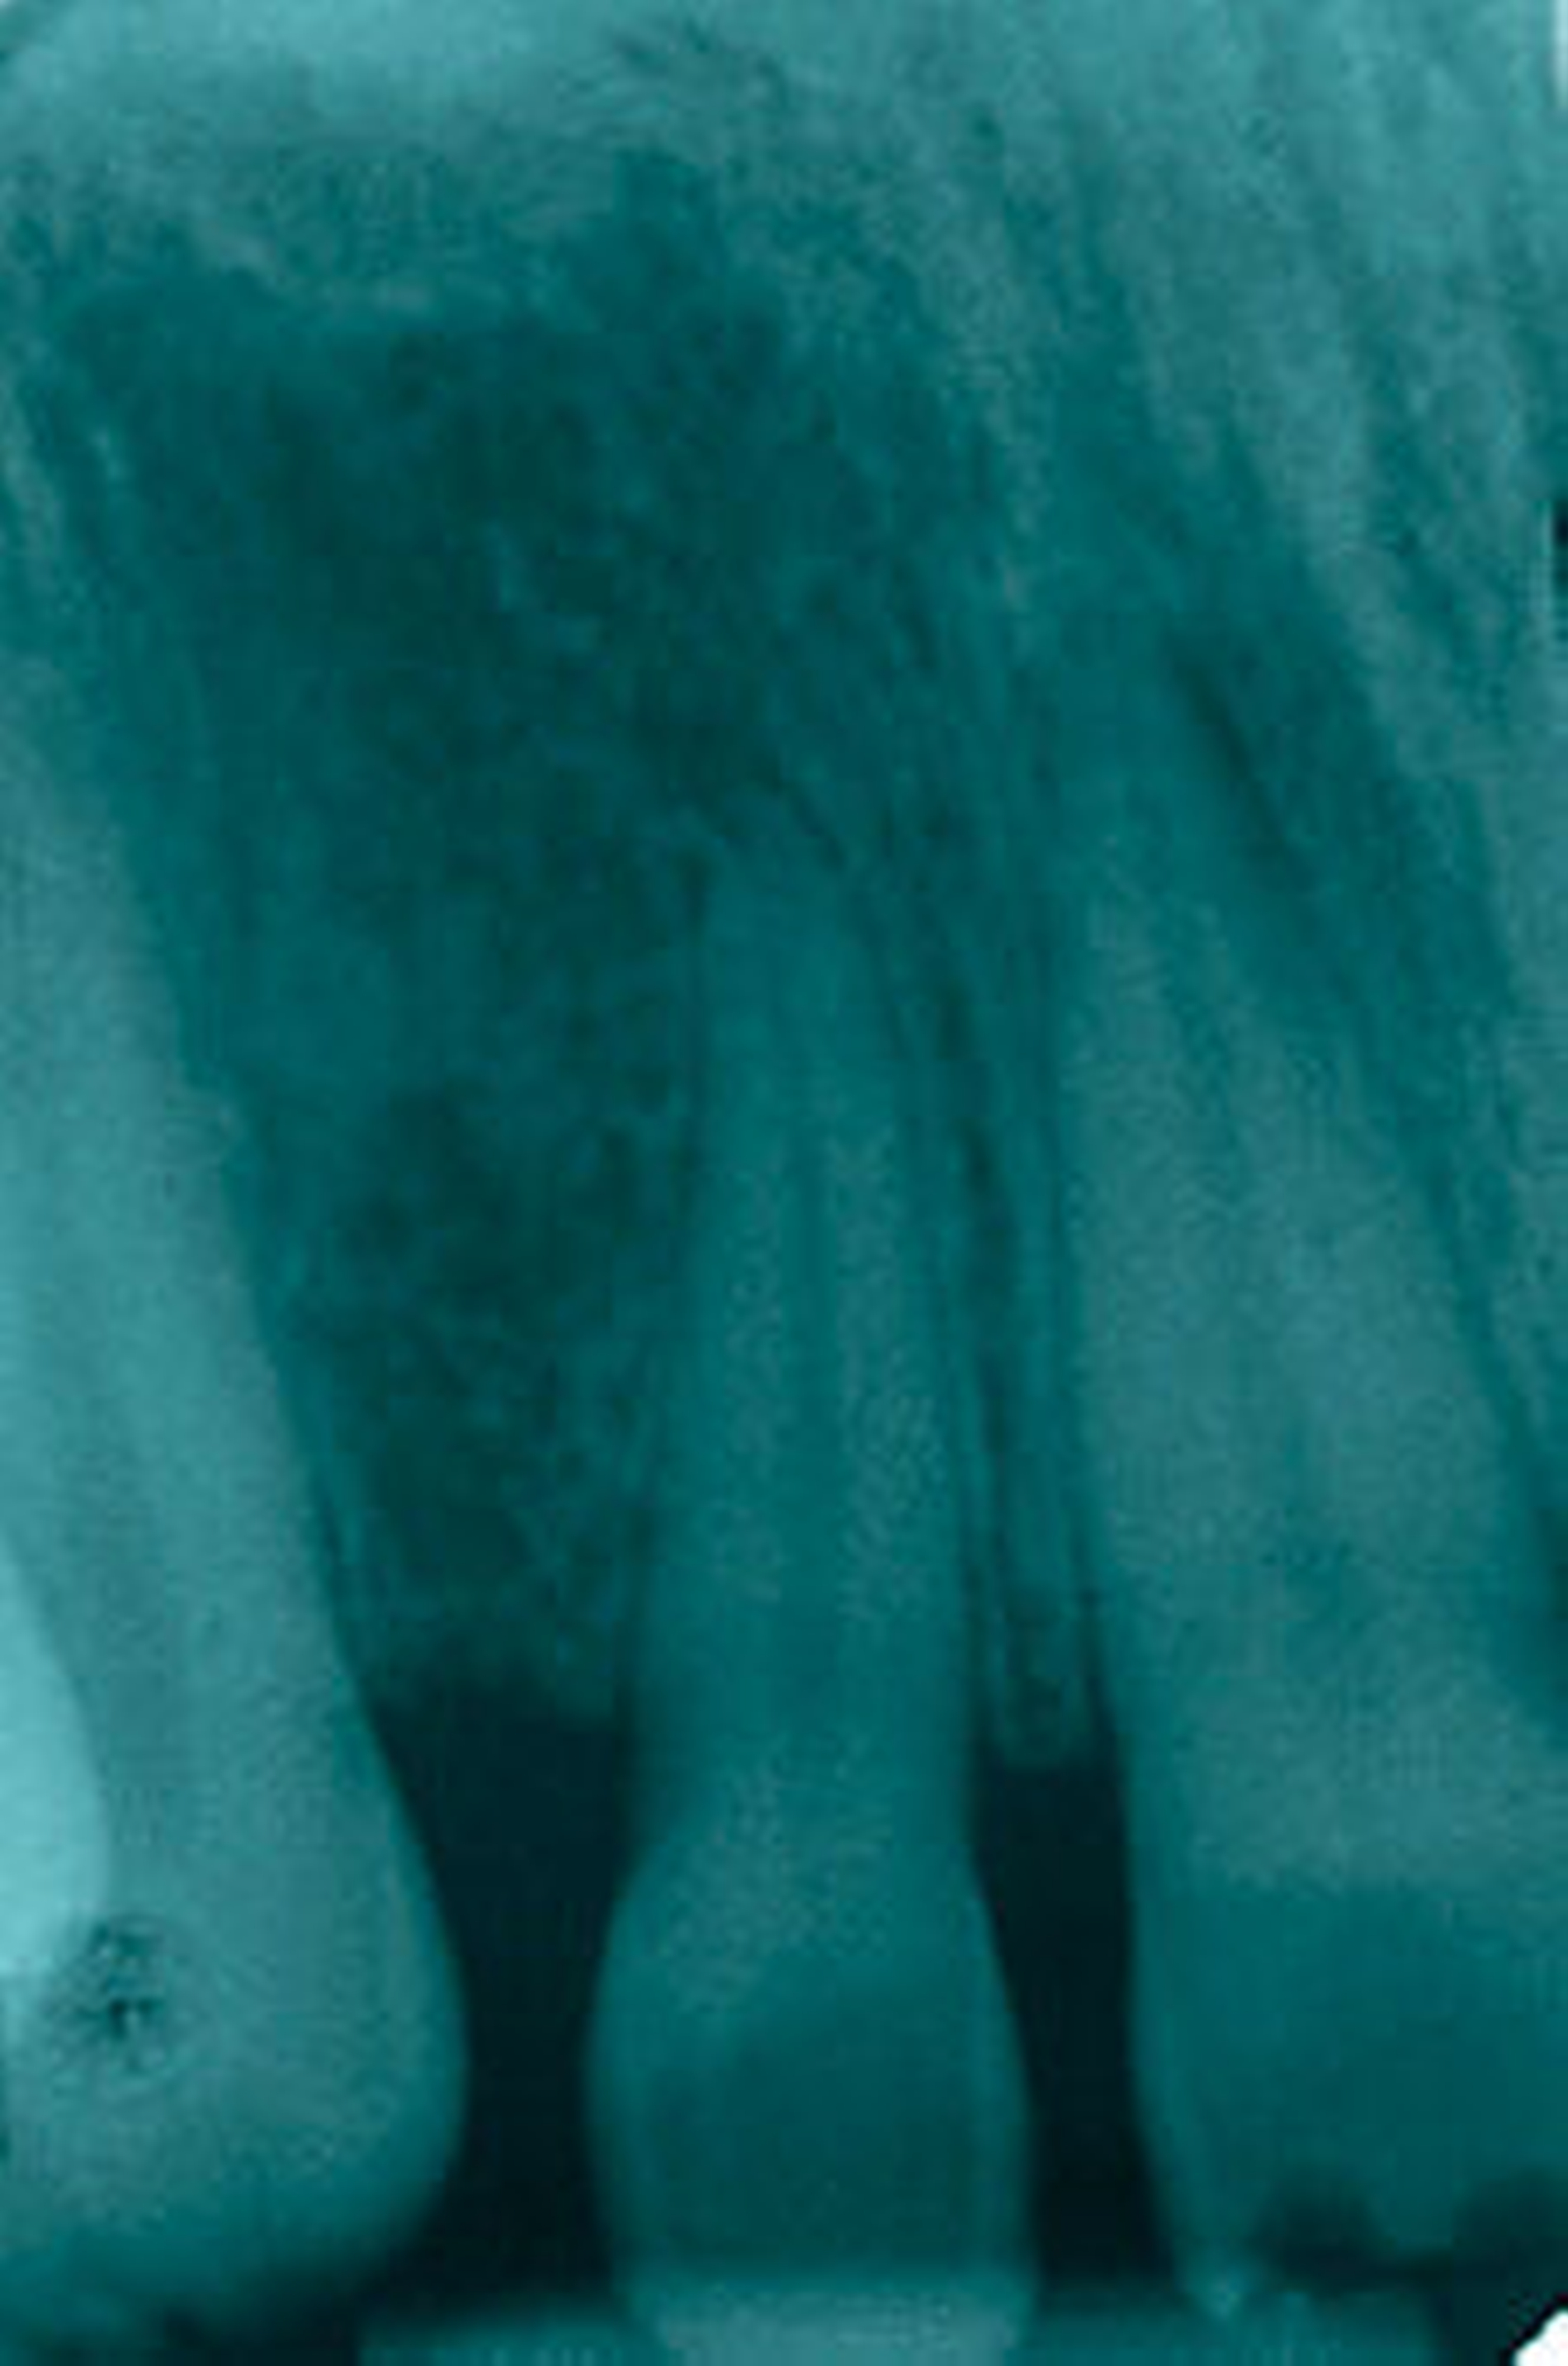

Röntgenbefunde:

Der Röntgenbefund ergab sich aus der Auswertung des bei Aufnahme der Patientin angefertigten Orthopantomogramms. Die Kiefergelenke stellen sich symmetrisch und regelgerecht dar. Die Kieferhöhlen erscheinen gut pneumatisiert. Es zeigten sich metallische Verschattungen im Sinne von Amalgamrestaurationen an den Zähnen 17, 46, 47, 36, 37. Die Zähne 16 und 26 weisen metallische Verschattungen mit einer röntgenopaken Begrenzung im Sinne von metallkeramischen Kronen auf. Vertikaler Knochenabbau findet sich an den Zähnen 17 distal und mesial, 16 distal und mesial, 15 distal, 25 distal, 26 mesial und distal, 27 mesial und distal, 36 distal, 37 mesial und distal, 47 mesial, 46 distal. Die Zähne 16, 27, 37, 38 und 47 weisen sub-gingivale Konkremente auf.